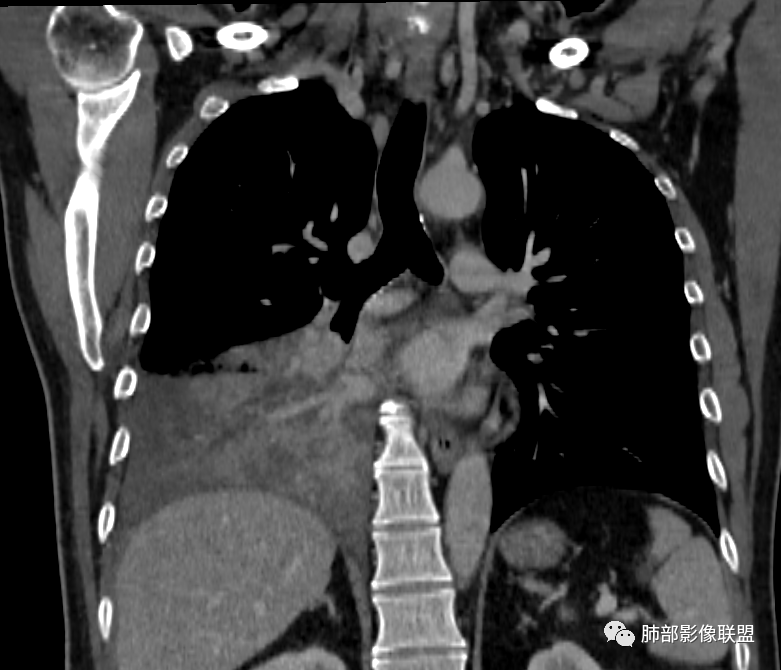

右肺下叶实变,周围磨玻璃,近端支气管扩张,管壁凹凸不平,远端阻塞,可见粘液栓,不均匀强化,有低密度无强化影,其内血管显示尚可,考虑粘液腺癌,鉴别淋巴瘤

右肺下叶大片实变,密度不均匀,可见支气管充气征及粘液区,右肺下叶支气管内结节影,下叶支气管阻塞,病灶前下可见磨玻璃影,右侧积液,考虑粘液腺癌,鉴别类癌?

右下叶支气管狹窄,内见高密度强化结节,远端大片不张实变,实变内可见多发粘液拴,整体观察实变似有见缝就针的感觉,综和分析考虑粘液表皮样癌,其次考虑类癌

冠状位重建有钻缝的感觉